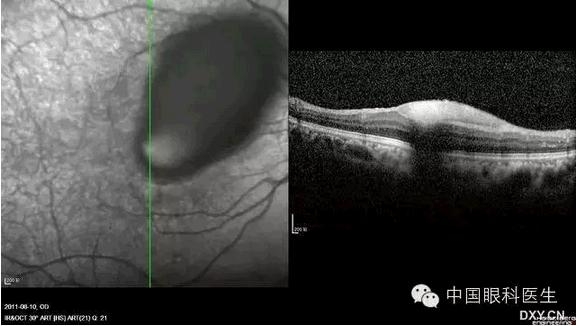

先天性黄斑缺损